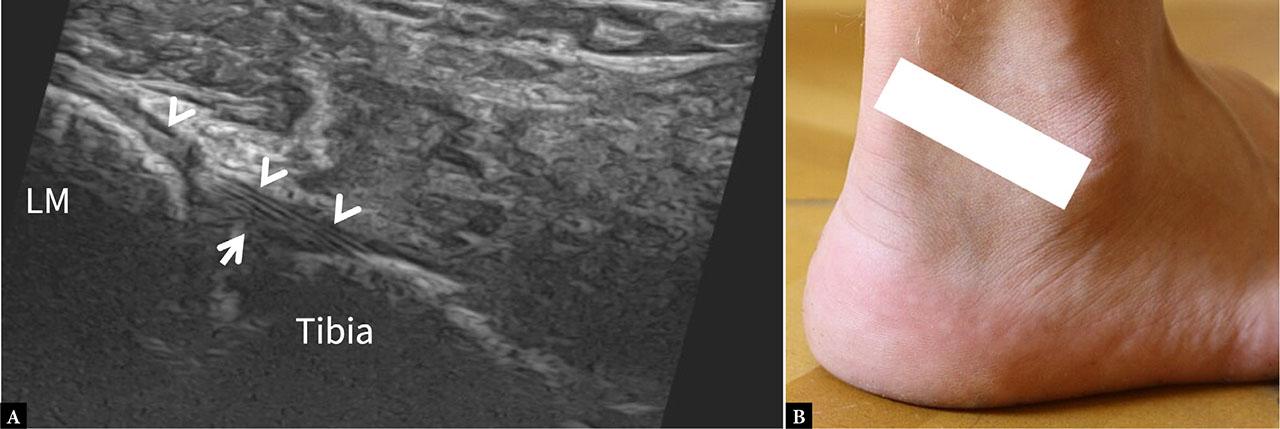

AiTFL: Visualized in an oblique axial plane extending from the tibial to the fibular tubercle. Appears as a thin, well-defined, fibrillar, echogenic band crossing the syndesmotic interval (Fig. 3).

US image of the superior (A) and (B) bands of the AiTFL. The ligament appears as continuous, fibrillar, hyperechoic bands with defined margins (arrows), extending from the anterior aspect of the lateral malleolus to the anterolateral aspect of the distal tibia. The US probe is oriented obliquely at 35° from the anterior aspect of distal tibia to the lateral malleolus (C)